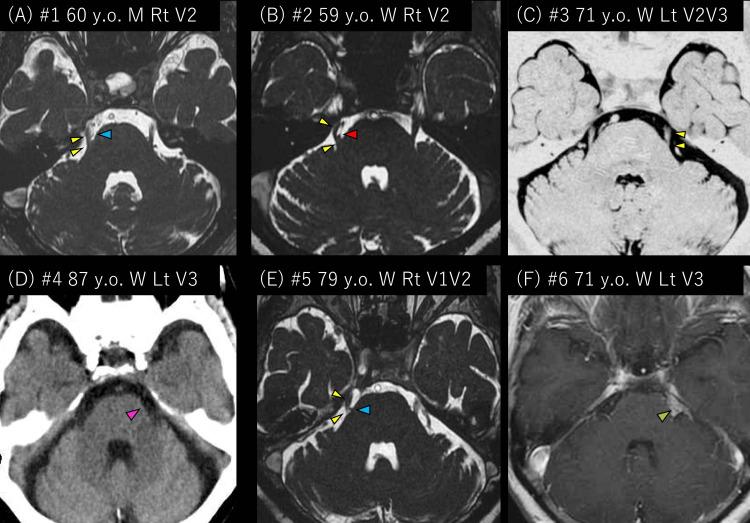

Background Surgical treatment for trigeminal neuralgia (TN) sometimes becomes difficult. Erenumab, an anti-calcitonin gene-related peptide (CGRP)-receptor monoclonal antibody, is used for migraine and potentially has efficacy for TN. Method We retrospectively investigated six migraine patients with comorbidity treated with 70 mg of erenumab. Monthly headache days and a numerical rating scale (NRS) of TN were evaluated before, one, and three months after erenumab administration. Results Before being treated with 70 mg of erenumab, the six migraine patients with comorbid TN had taken at least one sort of preventative medication, but it had been ineffective. During the three-month erenumab use, previous medications were continued. The median age was 71 years (range 59-87). The six patients (five females and one male) had episodic migraine. Three had TN due to vessels, one had TN due to a tumor, one had TN without neurovascular compression, and one had an undetermined etiology. Five (83%) of the six patients reported improved NRS of TN. The median NRS of TN before, one, and three months after treatment were 8 (7-10), 3.5 (0-10), and 2 (0-5, n=4). Monthly headache days were 4 (4-10), 2.5 (0-4), and 1 (1-2, n=4). There were no side effects of erenumab. Conclusion Surgical treatment sometimes cannot be performed for those with TN. Our findings were preliminary and a bigger sample size is required for this study to draw firmer conclusions. However, it is possible, although rare, that there are migraine patients for whom the NRS of comorbid TN improves with the use of erenumab, an anti-CGRP receptor monoclonal antibody.